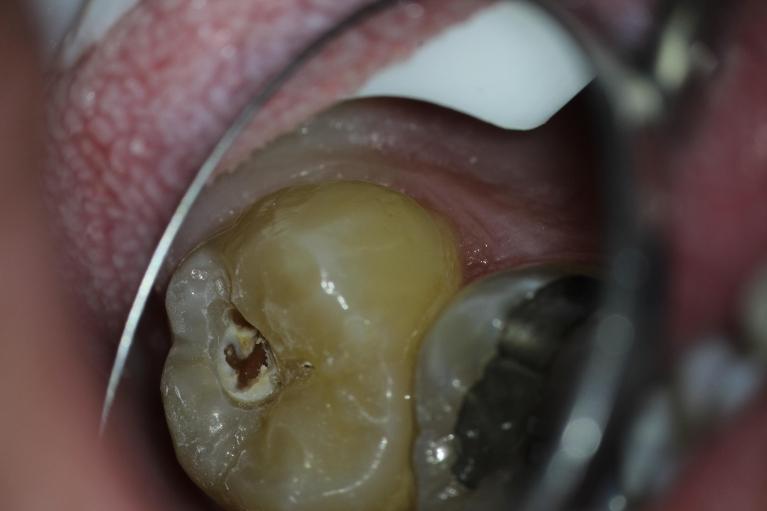

Welcome to our smile gallery, where you can browse photos of some of our best work. We hope that you find inspiration here for what is possible for your own smile. If you are considering cosmetic dentistry or you need help getting on track with your oral health, we look forward to hearing from you.

In the meantime, enjoy our before-and-after photos. We look forward to providing you with the same exceptional results.